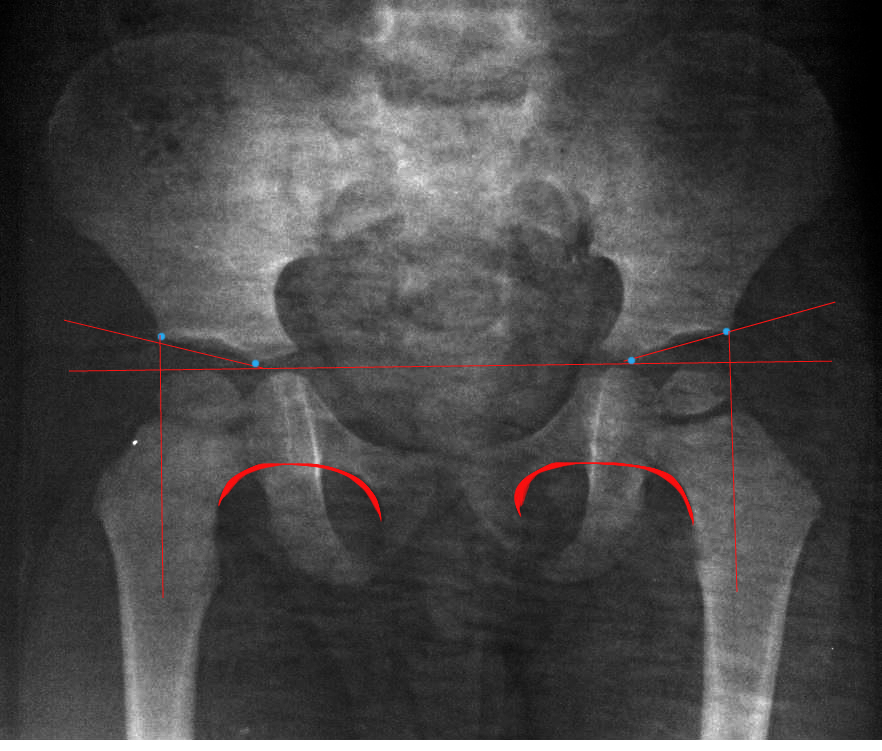

Рентген ТБС: Нормальные показатели

Раздел: Необычные решения